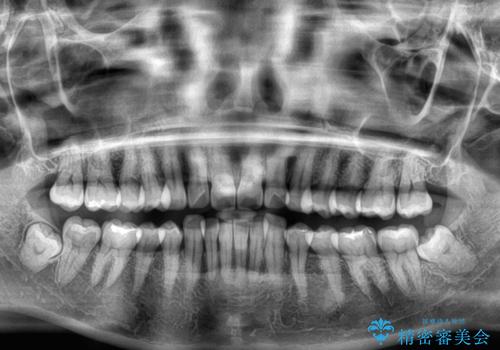

- 上下前歯の叢生を気にして来院された患者様です。

軽度な叢生であり、安価で短期間の治療を規模されていたため、インビザライン・モデレートを用いて矯正治療を行うこととしました。